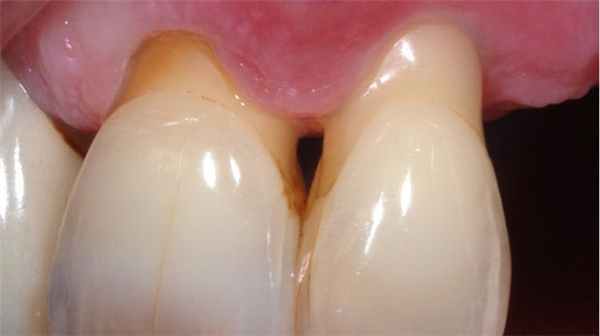

Пародонтит

Пародонтит - воспаление околозубной ткани и связочного аппарата, часто является последствием невылеченного гингивита. В тяжелых случаях затрагивает костную ткань.

К симптомам пародонтита относятся:

образование твердых зубных камней, они могут выделять гной;

оголенные зубные шейки;

боль при надавливании на подвижные зубы;

отверстия между зубами и деснами;

возникновение флюса при попадании инфекции в воспаленный зубной карман.